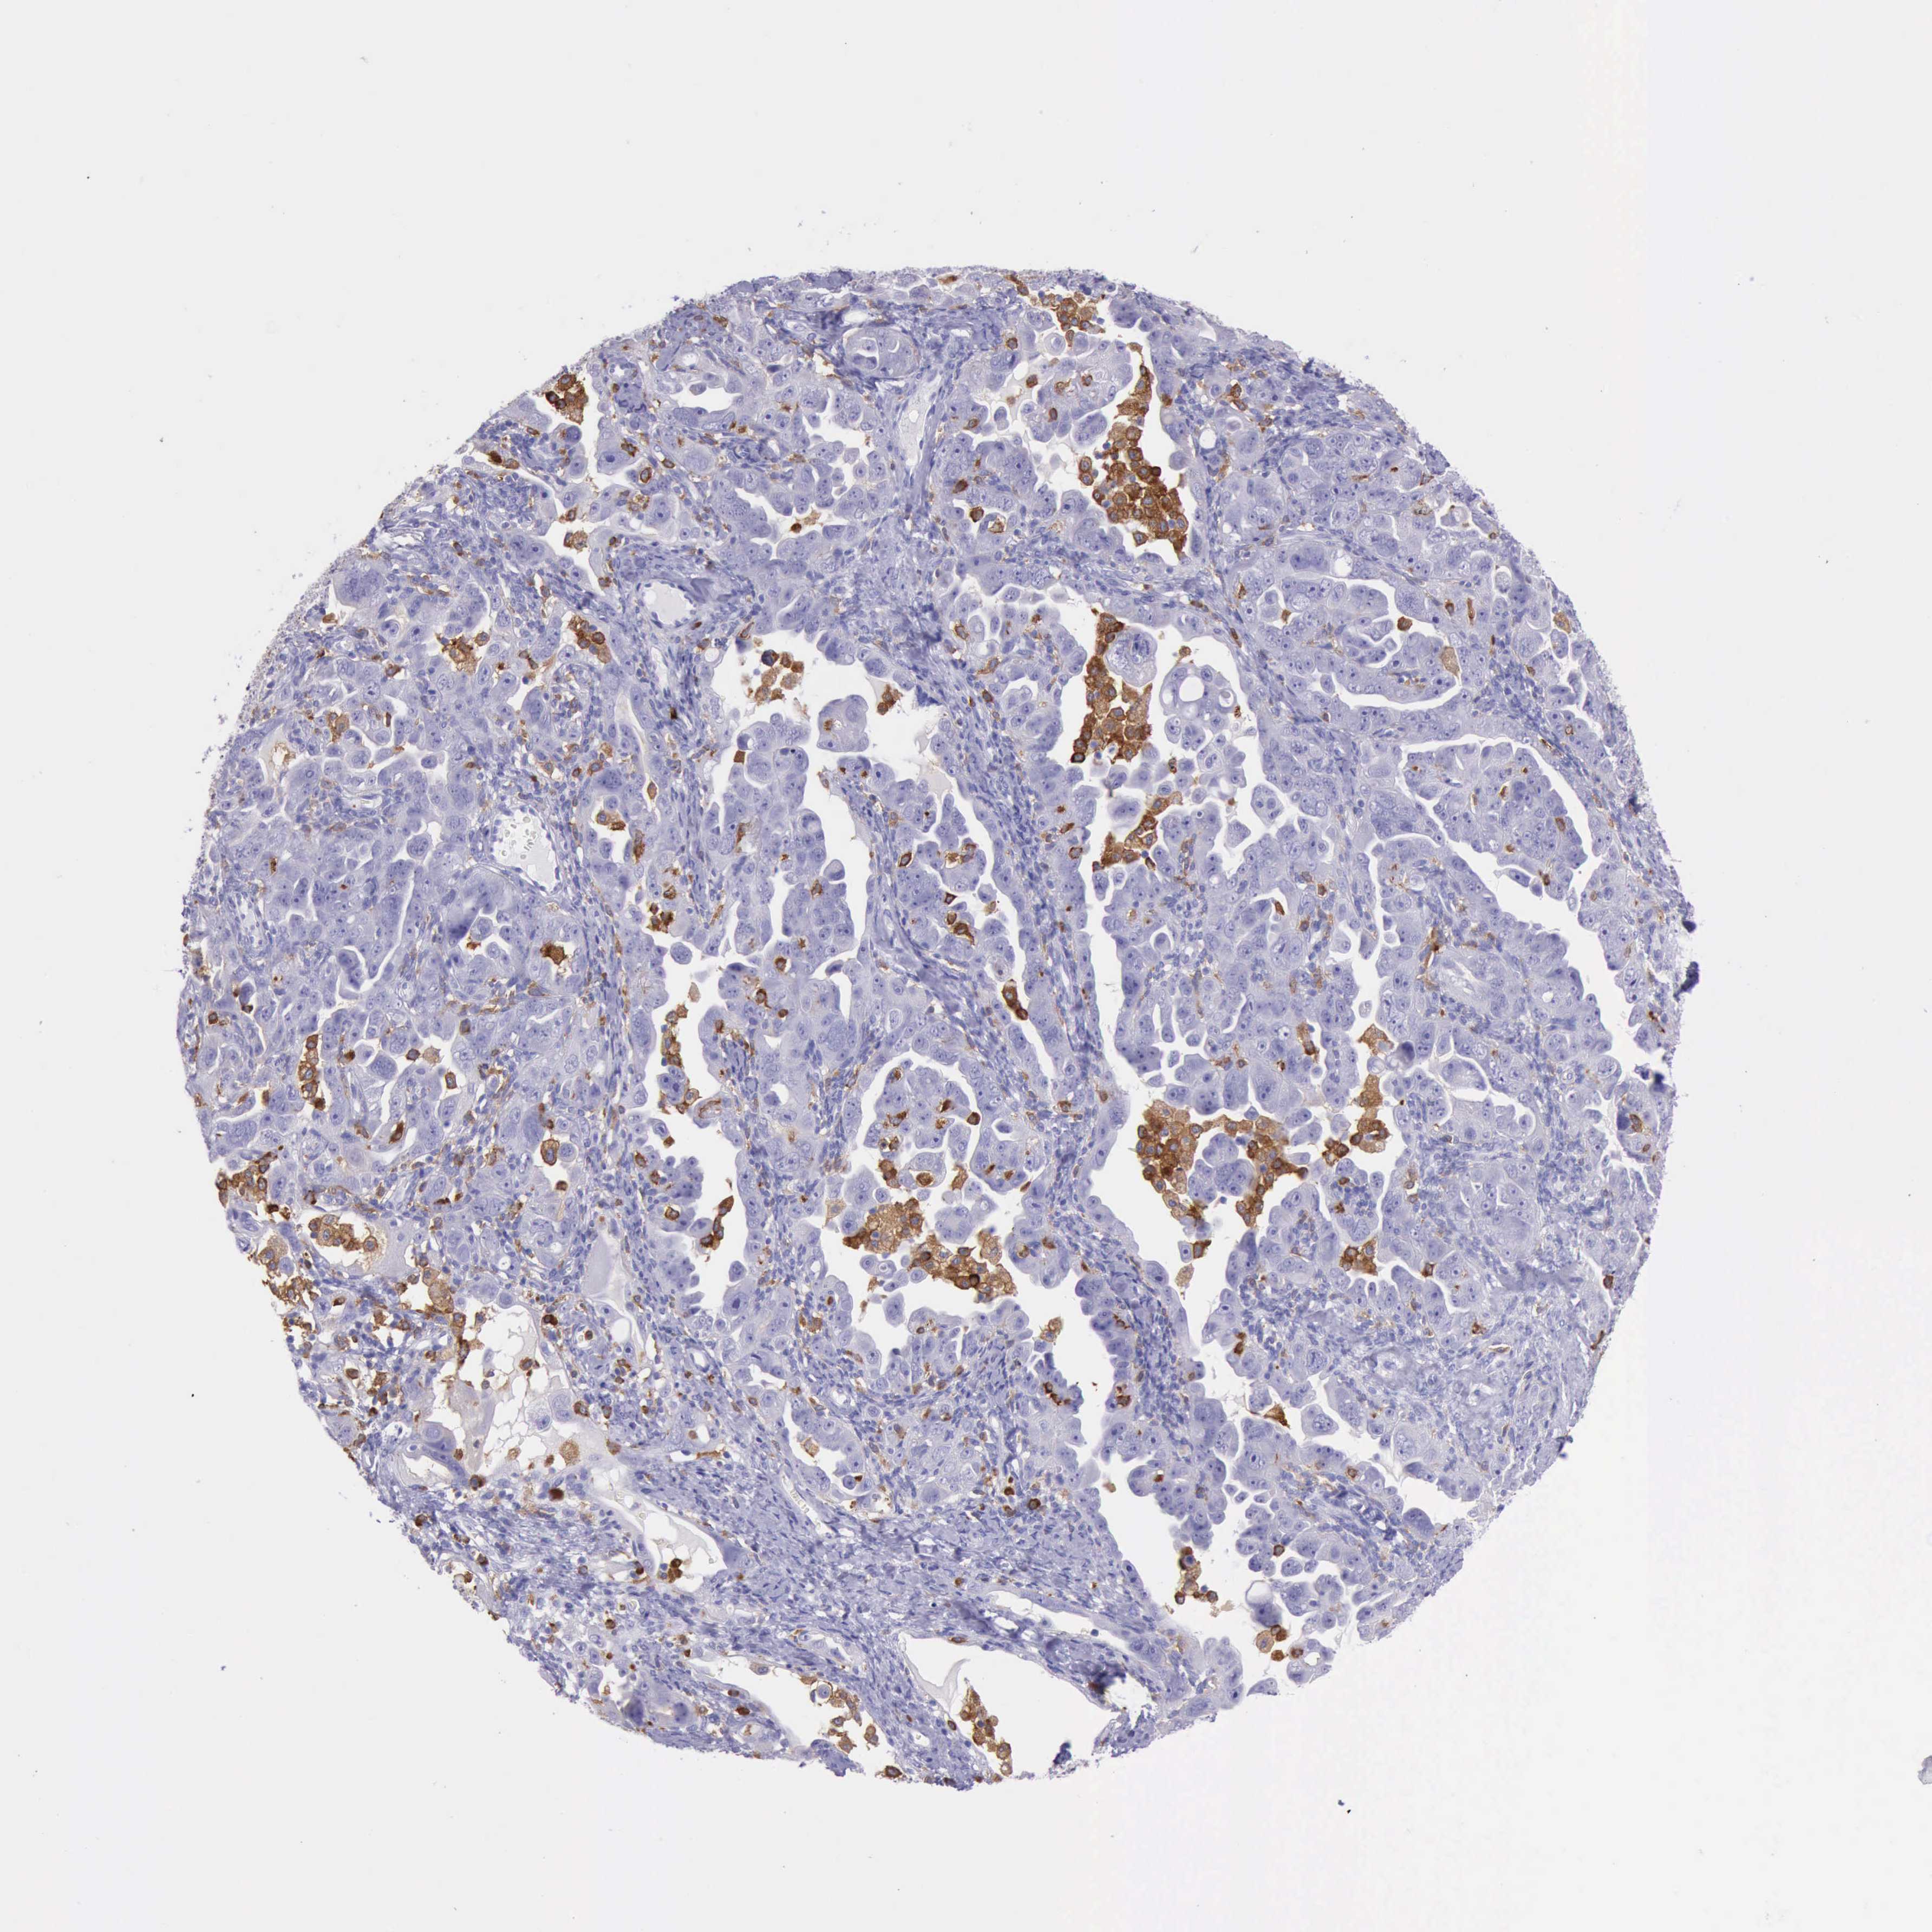

OVARIAN CANCER - Protein expressioni

A mouse-over function shows sample information and annotation data. Click on an image to view it in a full screen mode. Samples can be filtered based on level of antibody staining by selecting one or several of the following categories: high, medium, low and not detected. The assay and annotation is described here.

Note that samples used for immunohistochemistry by the Human Protein Atlas do not correspond to samples in the TCGA dataset.

Antibody stainingi

Antibody staining in the annotated cell types in the current human tissue is reported as not detected, low, medium, or high, based on conventional immunohistochemistry profiling in selected tissues. This score is based on the combination of the staining intensity and fraction of stained cells.

Each image is clickable and will lead to virtual microscopy that enables deeper exploration of all samples and also displays staining intensity scores, fraction scores and subcellular localization as well as patient and tissue information for each sample.

Antibody HPA001198

Antibody HPA002028

Antibody CAB016689

Antibody CAB080300

Cystadenocarcinoma, mucinous, NOS

Carcinoma, endometroid

Cystadenocarcinoma, serous, NOS

Carcinoma, NOS